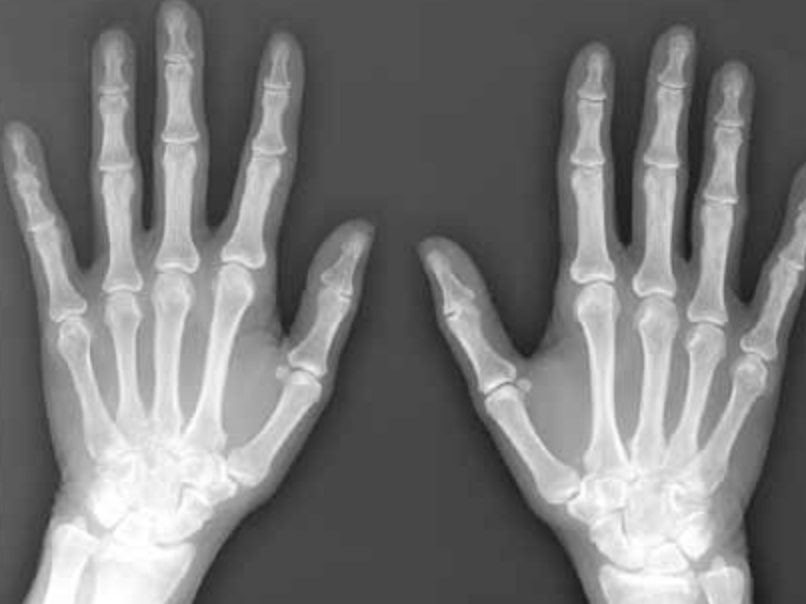

While it’s widely assumed that osteoporosis is a natural part of aging, that’s actually not true. What is true is that May is National Osteoporosis Month. It’s therefore a good time to learn the facts and actions you can take to sustain bone health and avoid bone breaks. It’s been estimated that 54 million US adults are at risk for osteoporosis and that ½ of our adult population is at risk for breaking a bone. Seniors who break bones, especially hips, are at increased risk for isolation, institutional living and even additional illness or earlier death. The importance of strong bones cannot be overemphasized. To learn some basics about good bone health, Read This.